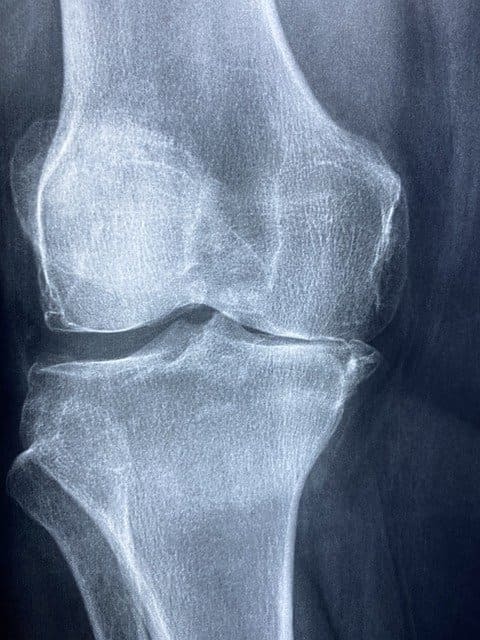

膝蓋下脂肪体炎は、膝関節にある膝蓋下脂肪体に炎症が起きること

膝蓋下脂肪体炎は、膝関節にある膝蓋下脂肪体に炎症が起きることです。フォッファ病と呼ばれることもあります。

膝蓋下脂肪体炎では、膝の前面やお皿の下あたりの膝に痛みが起こります。痛みは、膝関節に脂肪体が挟まれることによって起こります。

膝蓋下脂肪体は膝関節を機能させるために非常に大きな役割を果たしている組織です。そのため、膝蓋下脂肪体に炎症が起きることによって膝の動きに問題が起きたり痛みや違和感が現れたりするのです。

膝蓋下脂肪体とは

膝蓋下脂肪体は、膝のお皿の裏にある脂肪組織です。膝蓋下脂肪体は、スムーズに膝の曲げ伸ばしを行う働きをしています。

他にも、膝への衝撃を和らげるクッションとしての働きやお皿の可動性をよくする働き、膝関節の内圧を調整し一定に保つ働きをしています。

膝の前面にはいろいろな組織がありますが、中でも膝蓋下脂肪体は血管が多くあり痛みや炎症を起こしやすい組織であると言われています。